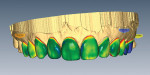

As shown in the immediate postoperative view of the cemented ceramics (Figure 8), highly variable margin placement was required to conservatively treat the multiple rotations, ectopic displacements, and existing restorations to yield a harmonious smile.